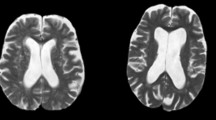

By superimposing all particle tracks from each experiment (Fig. 1b), we can estimate the extent of the PVSs: each is ~40 µm wide, comparable to the adjacent artery. Volumetric images using a dextran CSF tracer confirmed this result (Fig. 2a), and orthogonal projections showed two non-connecting PVSs, one on each side of the artery, with tracer excluded from the outer vessel wall (Fig. 2b, c). The PVS size and shape that we observe agree with in vivo measurements published previously (Fig. 2d)29,28,30 and do not depend on whether PVSs are imaged through a cranial window or a thinned skull (Supplementary Fig. 2). Identifying the specific structures that bound the observed PVSs is a worthy topic for future study.

Perivascular spaces (PVSs) are larger in vivo and collapse after fixation. a Fluorescent dextran in the CSF confirms the size of the PVS in vivo. b Cross-section at the dashed line in a, showing two PVSs with tracer. c Cross-sections proximal, across, and distal to a bifurcation show that the non-connecting PVS structure continues. d Average measurements of the width of the PVS from superimposed microsphere trajectories (e.g., Fig. 1b). Mean ± SEM, n = 13 mice. e To test whether the PVS and CSF tracer distribution were modified during tissue processing, we perfusion fixed a live anesthetized mouse with f phosphate-buffered saline (PBS) followed by g 4% paraformaldehyde (PFA) to h fix the tissue (Supplementary Movie 1). Diagrams are included below each image indicating our observations. Scale bar: 30 µm. i The vasculature was labeled with a lectin in the PBS perfusion solution and the same vessel in the same animal shown in a was imaged after fixation. It was necessary to remove dura to image the same vessels in situ due to the shrinkage of the brain. Small arrows point to a fold in the collapsed artery wall and tracer being redistributed around a pial vein. Overlapping lectin and dextran appear yellow. Scale bar: 40 µm. j Cross-section at the dashed line in i shows that after fixation, the vessel collapses and folds, and the tracer redistributes around the arterial wall. Scale bar: 20 µm. k To quantify the size of the PVS compared to that of the artery, we computed the ratios of the areas of the PVS and the adjacent artery for in vivo measurements utilizing tracked microspheres and dextran dye and after fixation (fixed). The lateral area of the PVS is roughly 1.4 ± 0.1 times larger than that of the artery itself in the live mice, and fixation reduces this ratio to about 0.14 ± 0.04. One-way analysis of variance (ANOVA) post hoc Tukey's test, ***P < 0.0002, ns not significant, mean ± SEM, n = 6–7/group

We did not observe tracers in the basement membranes of the arteries in our in vivo experiments, though prior studies of fixed tissue have observed them there1,3,22,24. Thus, we asked whether tracers enter the vessel wall during tissue processing. Perfusion fixation with 4% paraformaldehyde (PFA) caused abnormal retrograde flow and shrunk the PVS (Fig. 2e–h and Supplementary Movie 1), and also moved tracer from the perivascular space into the vessel wall (Fig. 2i, j). In vivo imaging showed that the cross-sectional area of the PVS is on average about 1.4 times that of the artery, whereas fixation reduced this ratio to 0.14 (Fig. 2k).